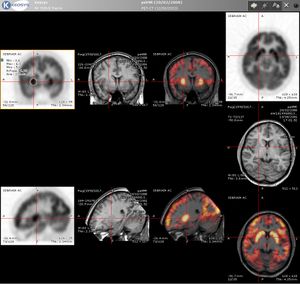

4. 2. 신경 영상

[18F]플루오로데옥시글루코스 (FDG)를 이용한 PET 영상은 뇌가 정상적으로 포도당을 빠르게 사용한다는 점을 이용한다. 뇌의 표준 FDG PET는 지역 포도당 사용량을 측정하며 신경병리학적 진단에 사용될 수 있다.[17]

알츠하이머병과 같은 뇌 병변은 포도당과 산소의 뇌 대사를 모두 크게 감소시킨다. 따라서 뇌의 FDG PET는 알츠하이머병을 다른 치매 과정과 구별하고 조기에 진단하는 데 사용될 수 있다. 알츠하이머병 진단을 위해 아밀로이드-베타 플라크를 영상화하는 방사성 추적자에는 플로르베타피르, 플루테메타몰, 피츠버그 화합물 B(PiB) 및 플로르베타벤이 있으며, 이들은 모두 뇌에서 아밀로이드-베타 플라크를 감지하는 데 사용된다.[18]

FDG를 이용한 PET 영상은 또한 "발작 초점"의 위치를 파악하는 데에도 사용할 수 있다. 발작 초점은 간발작 스캔 동안 저대사로 나타날 것이다.[19] 여러 방사성 추적자(즉, 방사성 리간드)가 특정 신경수용체 아형에 대한 리간드로 개발되었으며, 예를 들어 도파민 D2/D3 수용체에 대한 [11C]라클로프라이드, [18F]팔리프라이드 및 [18F]데스메톡시팔리프라이드, 세로토닌 수송체에 대한 [11C]McN5652 및 [11C]DASB, 세로토닌 5HT1A 수용체에 대한 [18F]메프웨이, 니코틴성 아세틸콜린 수용체 또는 효소 기질(예: AADC 효소)에 대한 [18F]니페네 및 6-FDOPA가 있다. 이러한 약물은 다양한 신경정신과적 및 신경 질환의 맥락에서 신경수용체 풀을 시각화할 수 있게 해준다.

해마 경화증의 진단에도 PET가 사용될 수 있다. FDG와 덜 흔한 추적자인 플루마제닐 및 MPPF가 이 목적으로 탐구되었다.[20][21] 경화증이 편측성(우측 해마 또는 좌측 해마)인 경우, FDG 섭취를 건강한 측면과 비교할 수 있다. 자기 공명 영상(MRI)로 진단하기 어려운 경우에도 PET로 진단할 수 있다.[22][23]

율리히 연구소에서는 2009년 4월 세계 최대 규모의 PET-MRI 장치가 가동을 시작했다. 이 장치는 9.4-테슬라 MRI 장치와 PET가 결합된 것이다. 현재 이러한 높은 자기장 세기에서는 머리와 뇌만 영상화할 수 있다.[72] 뇌 영상의 경우, N-로컬라이저라는 장치를 사용하여 통합 PET-CT 또는 PET-MRI 스캐너 없이 CT, MRI 및 PET 스캔을 등록할 수 있다.[73][74][75][76]